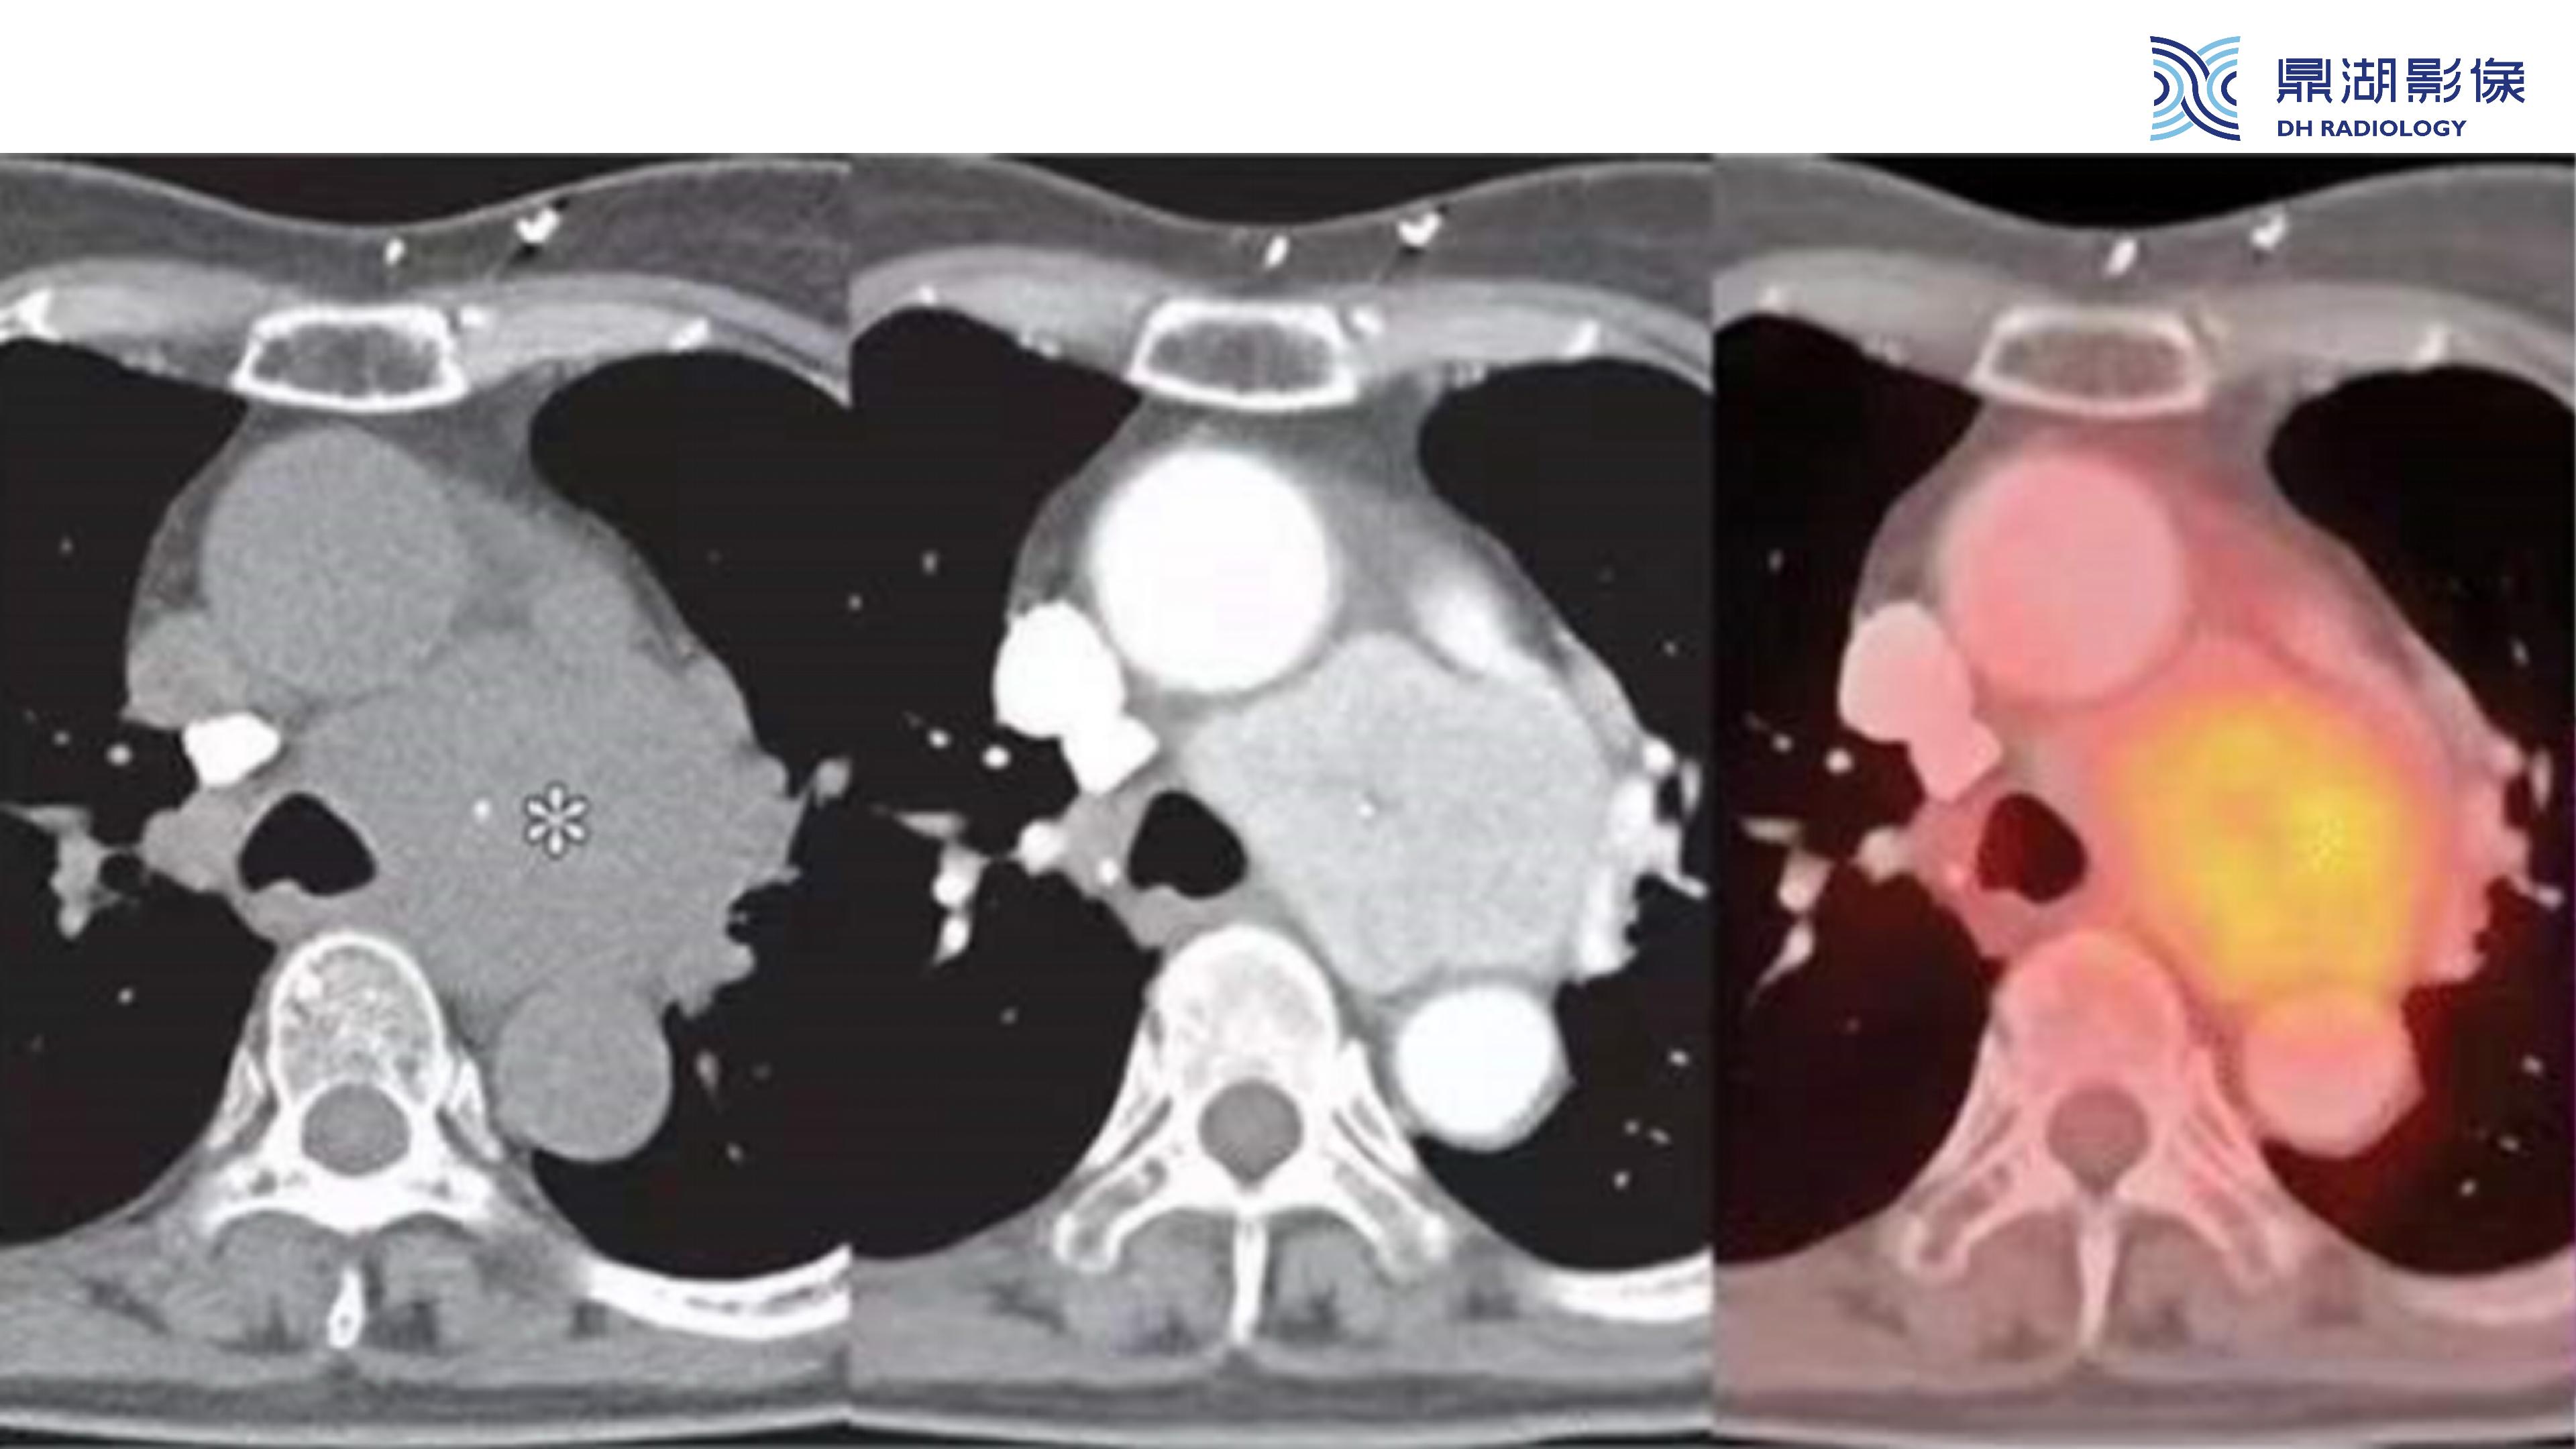

纵隔血管瘤-鼎湖社群读片病例